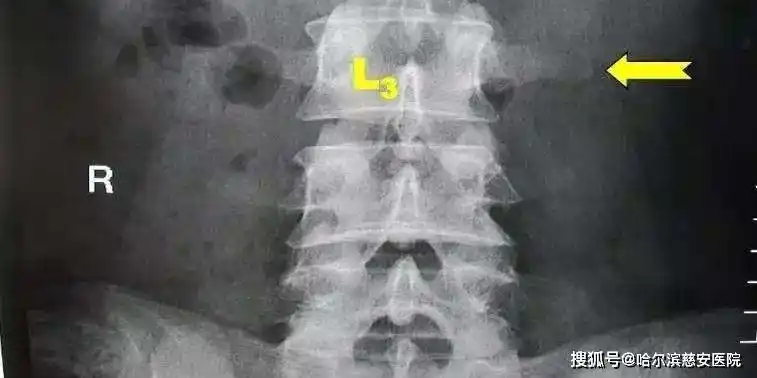

腰痛之第三腰椎横突综合症

科普第三腰椎横突综合征

经常腰痛的你也许得了腰三横突综合征

有一种腰痛叫腰三横突综合征

l3横突综合征ppt课件